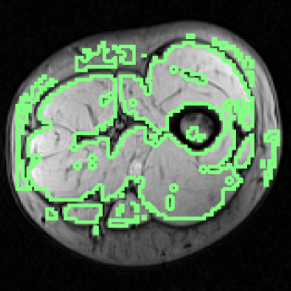

Refer to caption

Figure 4: Examples of AdaBoost muscle tissue segmentation results.

Mean and standard deviation of the mentioned performance measures were taken over a 10-fold cross-validation, and are presented in Fig. 3. Segmentation of the whole muscle region (Fig. 4) yielded mean Recall, Precision and Dice overlap coefficients of 0.81500.81500.8150, 0.74540.74540.7454 and 0.76230.76230.7623, respectively.

Average performance measures scored above 0.70.70.7, despite the variability on the results (Fig. 3). From the total 50 AdaBoost results obtained in cross-validation, the majority presented a correct identification of the muscle region, with proper tissue separation. Results with high recall rates tend to also increase the number of false positives (lower precision), as the example shown in Fig. 4(a). Using more features could improve the discriminative properties of the proposed classification scheme.

There is a codependency between AdaBoost accuracy and the atlas transformation and placement. Using the proposed atlas approach to label the AdaBoost binary leads to reasonable results in segmented images with a low false positive rate. However, if false positives have an influence on the position of the most distal point relative to the bone centroid, as shown in the example in Fig. 4(a), the proposed method tends to produce an unreliable muscle labeling. In these cases, the atlas transformation is biased and leads to labels offset, even though the AdaBoost segmentation recall rate is high (Figs. 5(a) and (b)).

Figure 5: Labeled skeletal muscle segmentation results.

When the recall rate is lower but precision in increased, muscle labels are, generally, placed correctly, despite the total segmented muscle area being slightly affected (Figs. 5(c) and (d)). Muscles with a smaller cross-sectional area in most of the used MRI, such as the Sartorius or the Rectus femoris, tend to be unrecognized on the labeled segmentation results if true positive recognition decays in those regions.